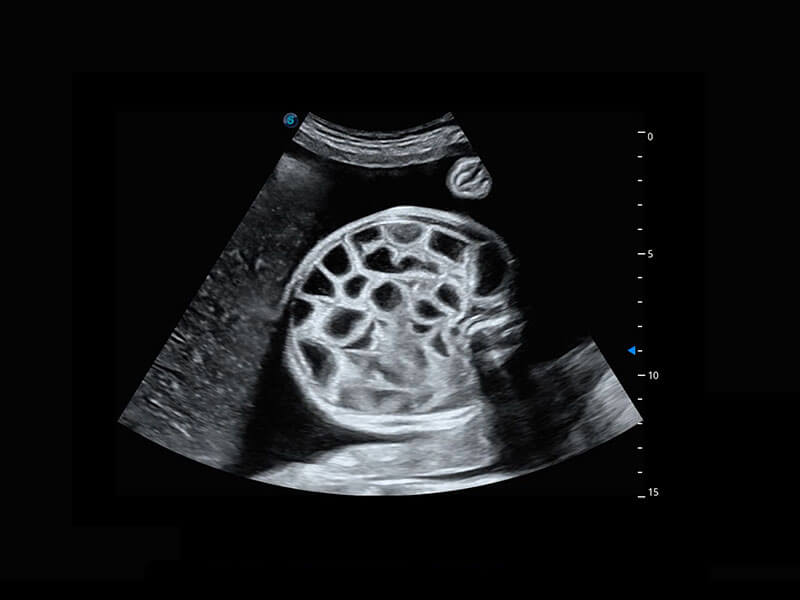

生殖健康

P60优异的图像质量搭载专科探头,在妇科基础疾病的诊断、卵泡生长的监测、输卵管通畅情况的判别等方面为您提供生殖应用方案。

• 腔内妇科-宫腔分离

• 腔内妇科-卵巢

• 腔内三维-宫内节育器

• 腔内三维-光影成像